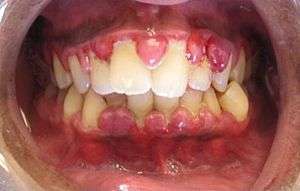

A case of gingivitis

Gingivitis ("inflammation of the gum tissue") is a non-destructive disease that occurs around the teeth.[1] The most common form of gingivitis, and the most common form of periodontal disease overall, is in response to bacterial biofilms (also called plaque) that is attached to tooth surfaces, termed plaque-induced gingivitis.

The symptoms of gingivitis are somewhat non-specific and manifest in the gum tissue as the classic signs of inflammation:

Additionally, the stippling that normally exists on the gum tissue of some individuals will often disappear and the gums may appear shiny when the gum tissue becomes swollen and stretched over the inflamed underlying connective tissue. The accumulation may also emit an unpleasant odor. When the gingiva are swollen, the epithelial lining of the gingival crevice becomes ulcerated and the gums will bleed more easily with even gentle brushing, and especially when flossing.